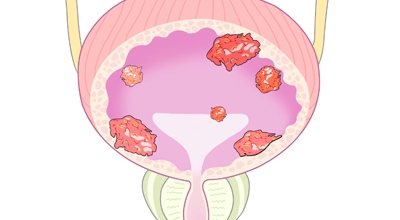

방광암이란

방광암은 여성보다 남성에게 발생할 확률이 상대적으로 높은 대표적 3대 비뇨기암으로 유명하고, 비뇨기계 암 중 발병률이 높아 남성암 중에선 7위라는 타이틀을 차지하고 있어요. 2017년 기준으로 보면 국내에서는 약 4400명이 방광암으로 진단받았으며 그중에서도 약 80프로가 고령 환자였다고 합니다.

방광암 초기증상